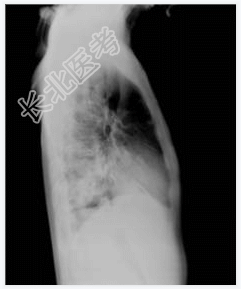

- [材料题] 男性,32岁,发热伴咳嗽、咳血丝痰一个多月,发热波动于38~39℃,外院拟肺炎抗炎治疗效果不著,入我院诊治。无盗汗,无咯血,体重下降10多斤,大小便正常。吸毒病史抽烟史10年。一般情况:无特殊。体查:右下肺湿啰音(小水泡音),二、三尖瓣听诊区闻及收缩期吹风样杂音2/6级。血常规:WBC 10.4,Ne82%。彩超:右心感染性心内膜炎,三尖瓣赘生物,重度三尖瓣漏,心包积液。痰肿瘤细胞学报告:未找到癌细胞。痰培养:无Ⅱ甲菌生长。